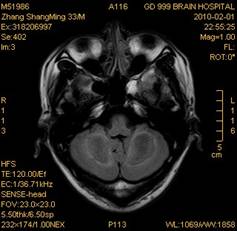

案例1 患者,男,33岁, 海洛因脑病的头颅MR。表现为双侧大脑后部皮层下白质、双侧内囊后肢、枕叶白质、胼胝体压部、中脑、桥脑、双侧小脑半球齿状核质及双侧桥臂多发对称性片状及斑片状长T1长T2异常信号影,FLAIR序列呈高信号,其中双侧内囊后肢表现为特异的“八字征”,双侧小脑半球齿状

核质表现为对称的“蝶翼征”,脑干病变呈“蟹钳征”及“中空征”。增强后双侧半卵圆中心、双侧枕叶白质及双侧小脑半球病变内或边缘中度强化影。给予患者抗炎、脱水、疏通血管及营养神经等药物治疗,一个月后痊愈出院。